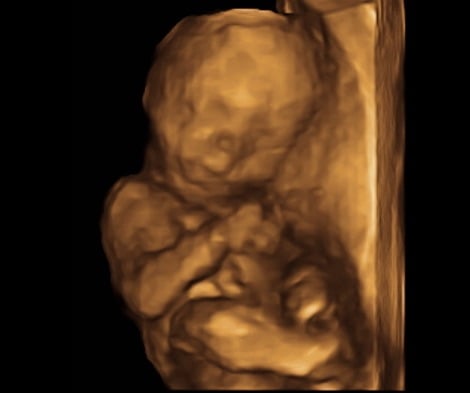

Bawling, unable to control myself any longer, we went back and got to see our little boy. I'm assuming my favourite nurse did some explaining because the technician was so nice and showed us everything, explaining it all, gently with compassion.

Baby boy is looking great, everything is as it should be. The relief I feel is honestly dizzying.

Though we aren't announcing his name to everyone, I love saying it, and would like to introduce Finn's little brother:

Oliver Heath M ❤️

I'm so in love. I can't stop staring at him.